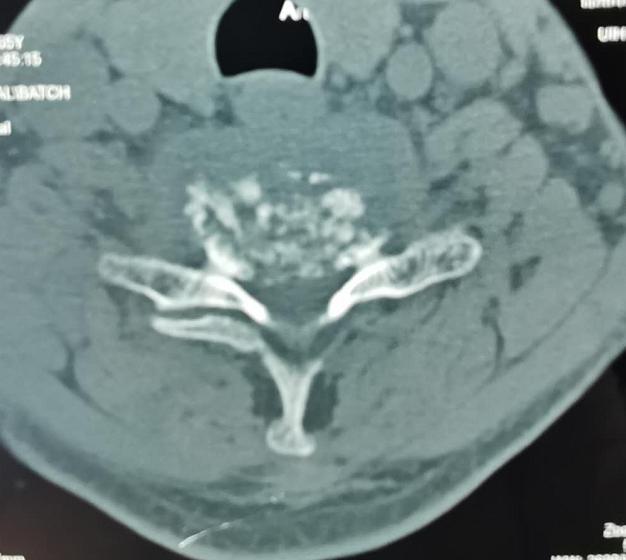

王先生今年64岁,入院时乳头以下全身麻木、不能走路、二便障碍,经核磁及CT检查发现“颈6椎体占位性病变”,且从发病至不能走路只经历约1个月时间,如不能得到及时治疗,患者出现高位截瘫的风险非常高。经市二院骨科医院骨八科主任田晓东(院长助理)及其团队的精心治疗,为患者进行颈胸段前后路联合手术、病灶清除内固定手术,术后一周,王先生感觉麻木消失,能自行下床活动,目前王先生恢复良好。

术前影像